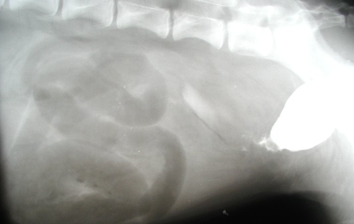

What is being shown in this Positive contrast cystography radiograph?

Bladder is small and is caudally positioned

Mineralised opacity of contrast medium

Contrast leaking into the abdomen (rupture)